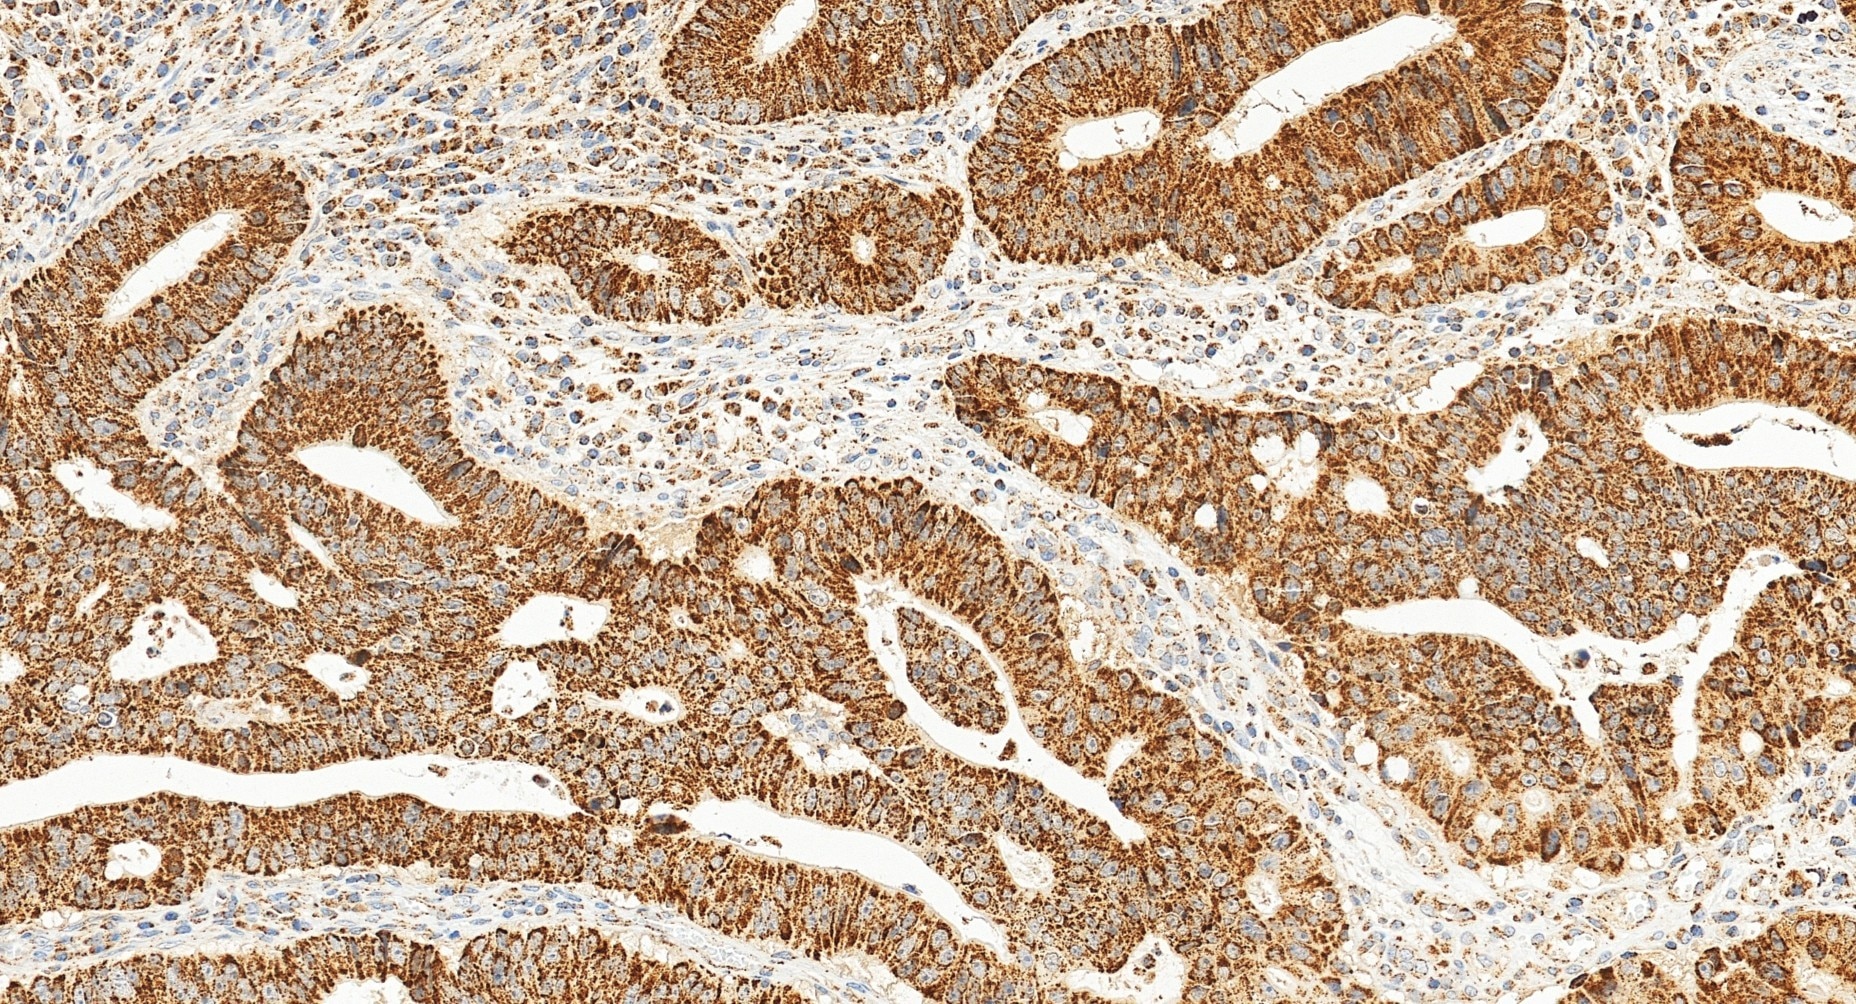

| Positive IHC detected in | human colon cancer tissue Note: suggested antigen retrieval with TE buffer pH 9.0; (*) Alternatively, antigen retrieval may be performed with citrate buffer pH 6.0 |

| Immunohistochemistry (IHC) | IHC : 1:1000-1:4000 |